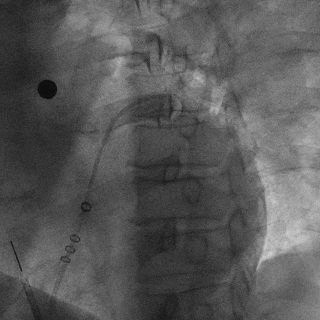

Lefort封堵器释放

封堵器释放前造影

下缘未露肩

符合Lefort释放原则,释放后造影,封堵器形态良好,未发生移动